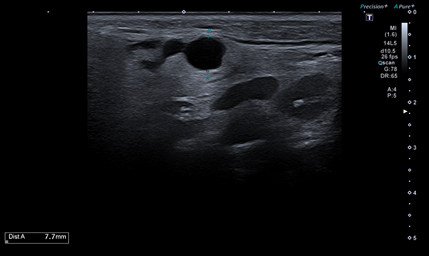

Hallazgos ecográficos

Se realiza ecografía clínica que muestra una imagen redondeada de márgenes regulares hipoecoica de 7,7 mm, sin tabicación y con refuerzo acústico posterior, que parece localizada en la glándula parótida derecha.

Señal doppler dudosa. Junto a esta lesión se visualiza otra de similares características, pero de menor tamaño.